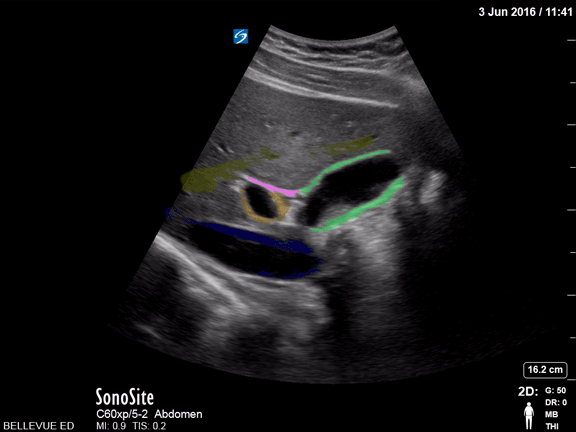

Biliary - Gallbladder and Commmon Bile Duct - Colorized

Gallbladder and Common Bile Duct Green: Gallbladder, Blue: IVC, Orange: Portal vein, Pink: Common bile duct, Yellow: Lumen of hepatic vein Images: Dr. Lindsay Davis, Dr. Hannah Kopinski. Image Editing: Michael Amador and Dr. Matthew Riscinti